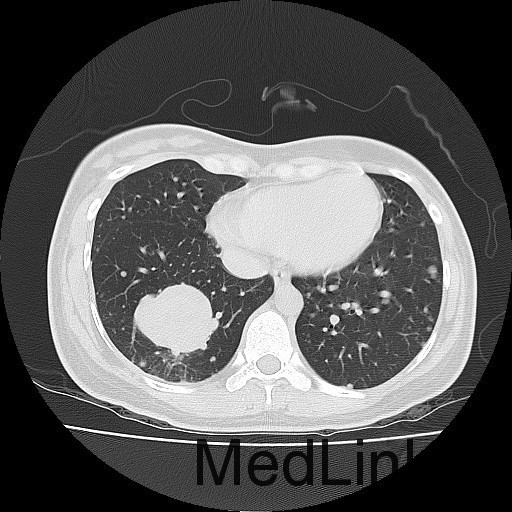

查体:右大腿上段较左侧增粗,后内侧皮下可触及大小约5*6cm肿物,质软,边界不清,活动度可,压痛(+),无波动感。 辅助检查:胸部CT:双肺多发转移瘤。

诊断:肺占位性病变(转移瘤?);大腿软组织疾患(右侧大腿肿物) 治疗:入院右下肢MR平扫+增强扫描:右侧大收肌软组织占位性病变,考虑间叶源性恶性肿瘤可能性大,血管源性可能?瘤周多发静脉曲张及侧枝循环形成,建议CT增强扫描进一步检查明确血管情况。遂于声引导下右大腿肿物穿刺活检,病理结果提示:(右大腿肿物)送检穿刺组织,肿瘤细胞形成器官样及腺泡状结构,细胞巢间为纤维性分隔,细胞呈大圆形、多边形,胞质丰富透亮,部分呈嗜伊红色,细胞核大,核分裂象少见,结合临床病史及免疫组化,考虑为腺泡状软组织肉瘤。免疫组化结果(①):CK(-),Vim(-),Ki-67(5%+),HMB45(-),MelanA(-),SMA(+),desmin(-),Myogenin(-),MyoD1(-),S100(-),NSE(部分+),CD56(-)。